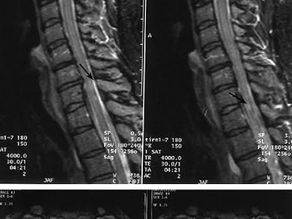

Zygoapophyseal joint pain

The facet joints are located on the back side of the vertebral column. They are formed by the inferior articular process of the superior...